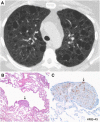

The diffuse cystic lung diseases (DCLDs) are a group of pathophysiologically heterogenous processes that are characterized by the presence of multiple spherical or irregularly shaped, thin-walled, air-filled spaces within the pulmonary parenchyma. Although the mechanisms of cyst formation remain incompletely defined for all DCLDs, in most cases lung remodeling associated with inflammatory or infiltrative processes results in displacement, destruction, or replacement of alveolar septa, distal airways, and small vessels within the secondary lobules of the lung. The DCLDs can be broadly classified according to underlying etiology as those caused by low-grade or high-grade metastasizing neoplasms, polyclonal or monoclonal lymphoproliferative disorders, infections, interstitial lung diseases, smoking, and congenital or developmental defects. In the first of a two-part series, we present an overview of the cystic lung diseases caused by neoplasms, infections, smoking-related diseases, and interstitial lung diseases, with a focus on lymphangioleiomyomatosis and pulmonary Langerhans cell histiocytosis.